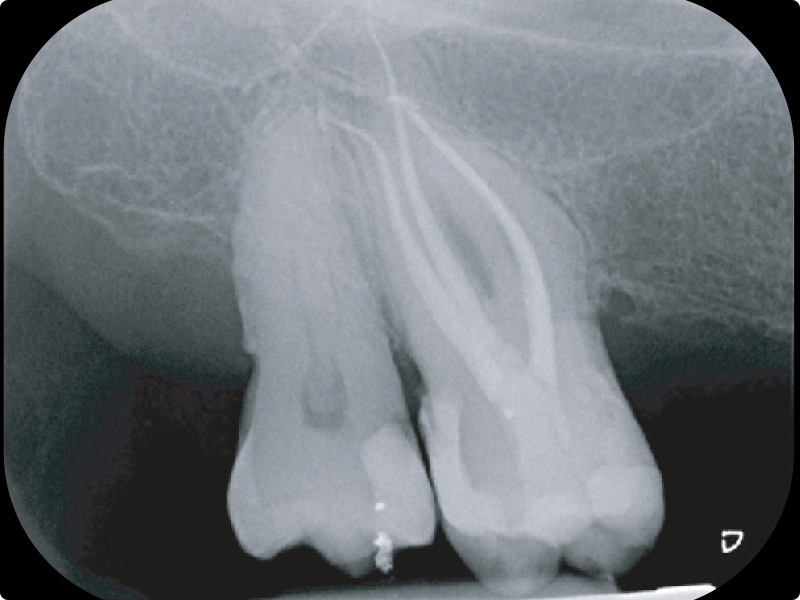

• Gestione dei canali calcificati e curvi:

• come evitare gli errori e raggiungere gli obiettivi

• La rifinitura apicale:

• lunghezza di lavoro

• gauging apicale

• visual gauging